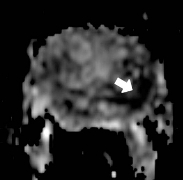

Figure 2 is biopsy proven prostate adenocarcinoma in a 62-year-old man with a Gleason grade of 6 (3+3). This example shows how functional imaging can help identify the tumor.

Figure 2b: Diffusion weighted image with ADC map shows a low ADC value in the left mid glaperipheral zone lesion (white arrow), indicative of prostate cancer.